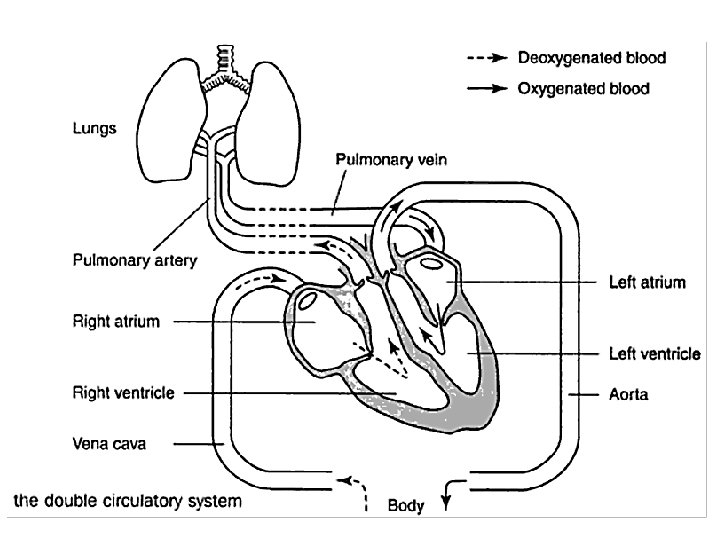

Circulation Summary • Consists of heart, blood and blood vessels • Double-circulation as blood travels twice through heart in one journey • Pulmonary circulation (heart lungs) • Systemic circulation (Heart body) • Oxygenated (O 2 rich) heart to body • Deoxygenated (O 2 poor) body to heart

Path of Oxygenated Blood • Pulmonary vein left atrium • Through mitral valve down into the left ventricle. • The ventricle then contracts forcing the mitral valve closed and opening the semilunar valve. • The blood then flows up into the aorta and around the body.

Path of Deoxygenated blood • Vena cava right atrium • Through tricuspid valve right ventricle. • Ventricle contracts, tricuspid valve closes, semilunar valve opens. • Blood flows to the pulmonary artery lungs.